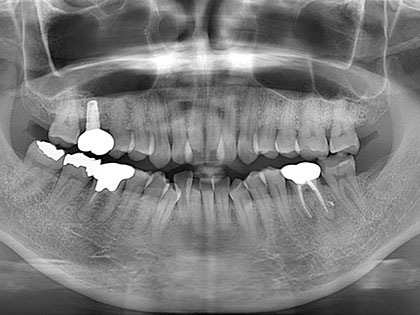

• 治療中の写真がこちら

• インプラント治療中1

• インプラント治療中2

• インプラント治療中3

• インプラント治療中4